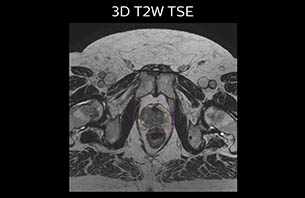

The MR images needed for RT planning are exported to the treatment planning system (TPS), where the MRCAT images are handled as a CT image set by the TPS, with no manual postprocessing required. Target and OAR delineation is performed using the T2-weighted images.

A 77-year-old male with prostate cancer cT3aN0M0, Gleason 8 and PSA 52 μg/L referred to androgen deprivation and radiation therapy with a prescribed dose of 50 Gy to the pelvic lymph node regions and 76 Gy to the prostate.

The 3D T1W FFE mDIXON sequence provides in-phase, water and fat images in one acquisition. Target and organs-at-risk are delineated on the 3D T2W TSE images. Prostate GTV is shown in orange, PTV in purple. The 3D bFFE sequence is used by the planner to mark the position of the fiducial markers (gold anchors) and contours are transferred to the digitally reconstructed radiographs (DRRs).